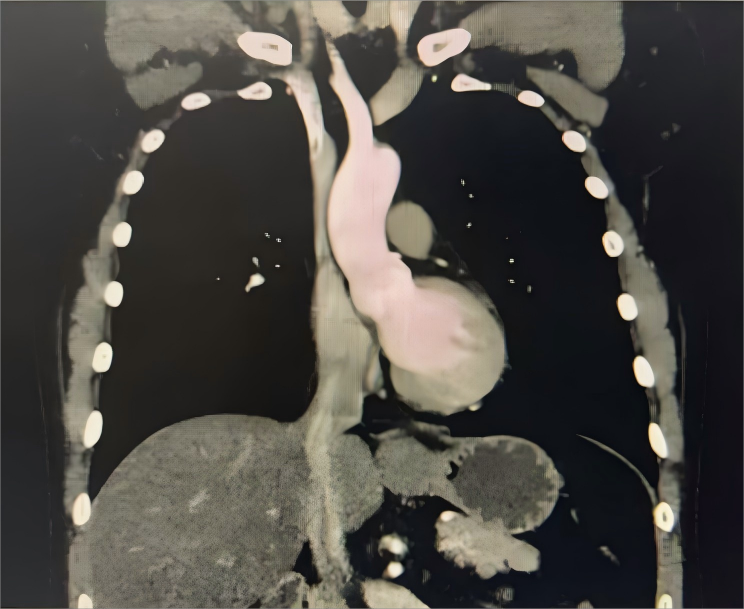

半月余前,患者吴先生于外院体检时发现食管下段肿物,虽无吞咽困难等症状,为求进一步诊治,经人介绍来到西安市第三医院。经消化内镜中心胃镜检查,考虑为食管良性肿瘤,随后转入胸外科接受治疗。

据该院胸外科主任杨锋介绍,食管良性肿瘤在食管肿瘤中仅占约1%,发病年龄较轻,症状进展缓慢。对于肿瘤较小、无明显临床症状的患者可暂时观察,但若肿瘤来源于肌层,则建议手术治疗。手术需精准把握解剖层次,避免损伤黏膜,降低术后并发症风险。

经全面评估并与消化内科专家共同讨论,一致认为患者手术指征明确,决定行腔镜辅助食管肿物切除术。术中,在麻醉科团队的全程护航下,消化内科专家通过胃镜精准定位肿瘤位置,胸外科手术团队精细操作,完整切除肿物并确认黏膜完好无损。